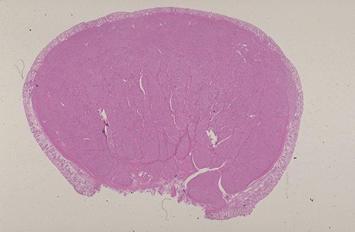

Rectal cartinoid tumor removed by an endoscopical polypectomy.

Tokyo Pref., Cooperative study between National Cancer Center and Kyushu Cancer Center

Carcinoid tumor/

Large intestine(Colon)/Rectum

Histology

1 - 9

submucosa